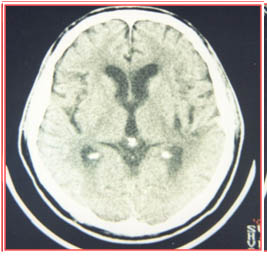

腦出血微創(chuàng)置管術,通過術前、術中精確定位,能夠很好地確定血腫部位,并避開重要腦組織功能區(qū)及重要血管,對周圍腦組織幾乎沒有影響,把手術創(chuàng)傷降到了最低。手術優(yōu)點是能夠有效的清除血腫,最大限度的減少周圍組織的損傷,及時解除了腦出血占位,降低了顱內壓,阻斷了腦出血后一系列繼發(fā)性病理生理改變所導致的惡性循環(huán)。對減輕腦水腫、防止再次出血,防治肺部感染、上消化道出血等并發(fā)癥的發(fā)生有顯著作用。由于手術創(chuàng)傷小、手術時間短、血腫引流確切,患者恢復快、住院時間短、花費少。改變了以往傳統(tǒng)開顱手術風險高,手術時間長,患者創(chuàng)傷大,并發(fā)癥多,恢復慢的問題。

術后第1天